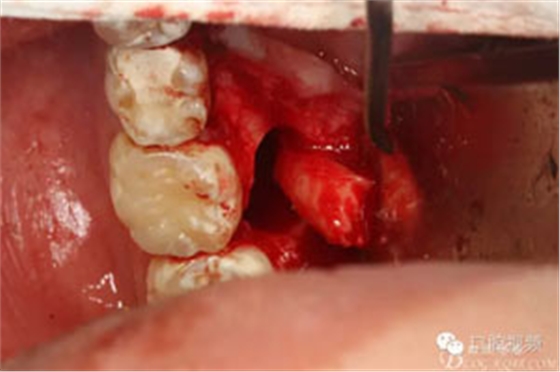

圖11.清理拔牙創(chuàng)。

圖12.取出是埋伏牙牙根